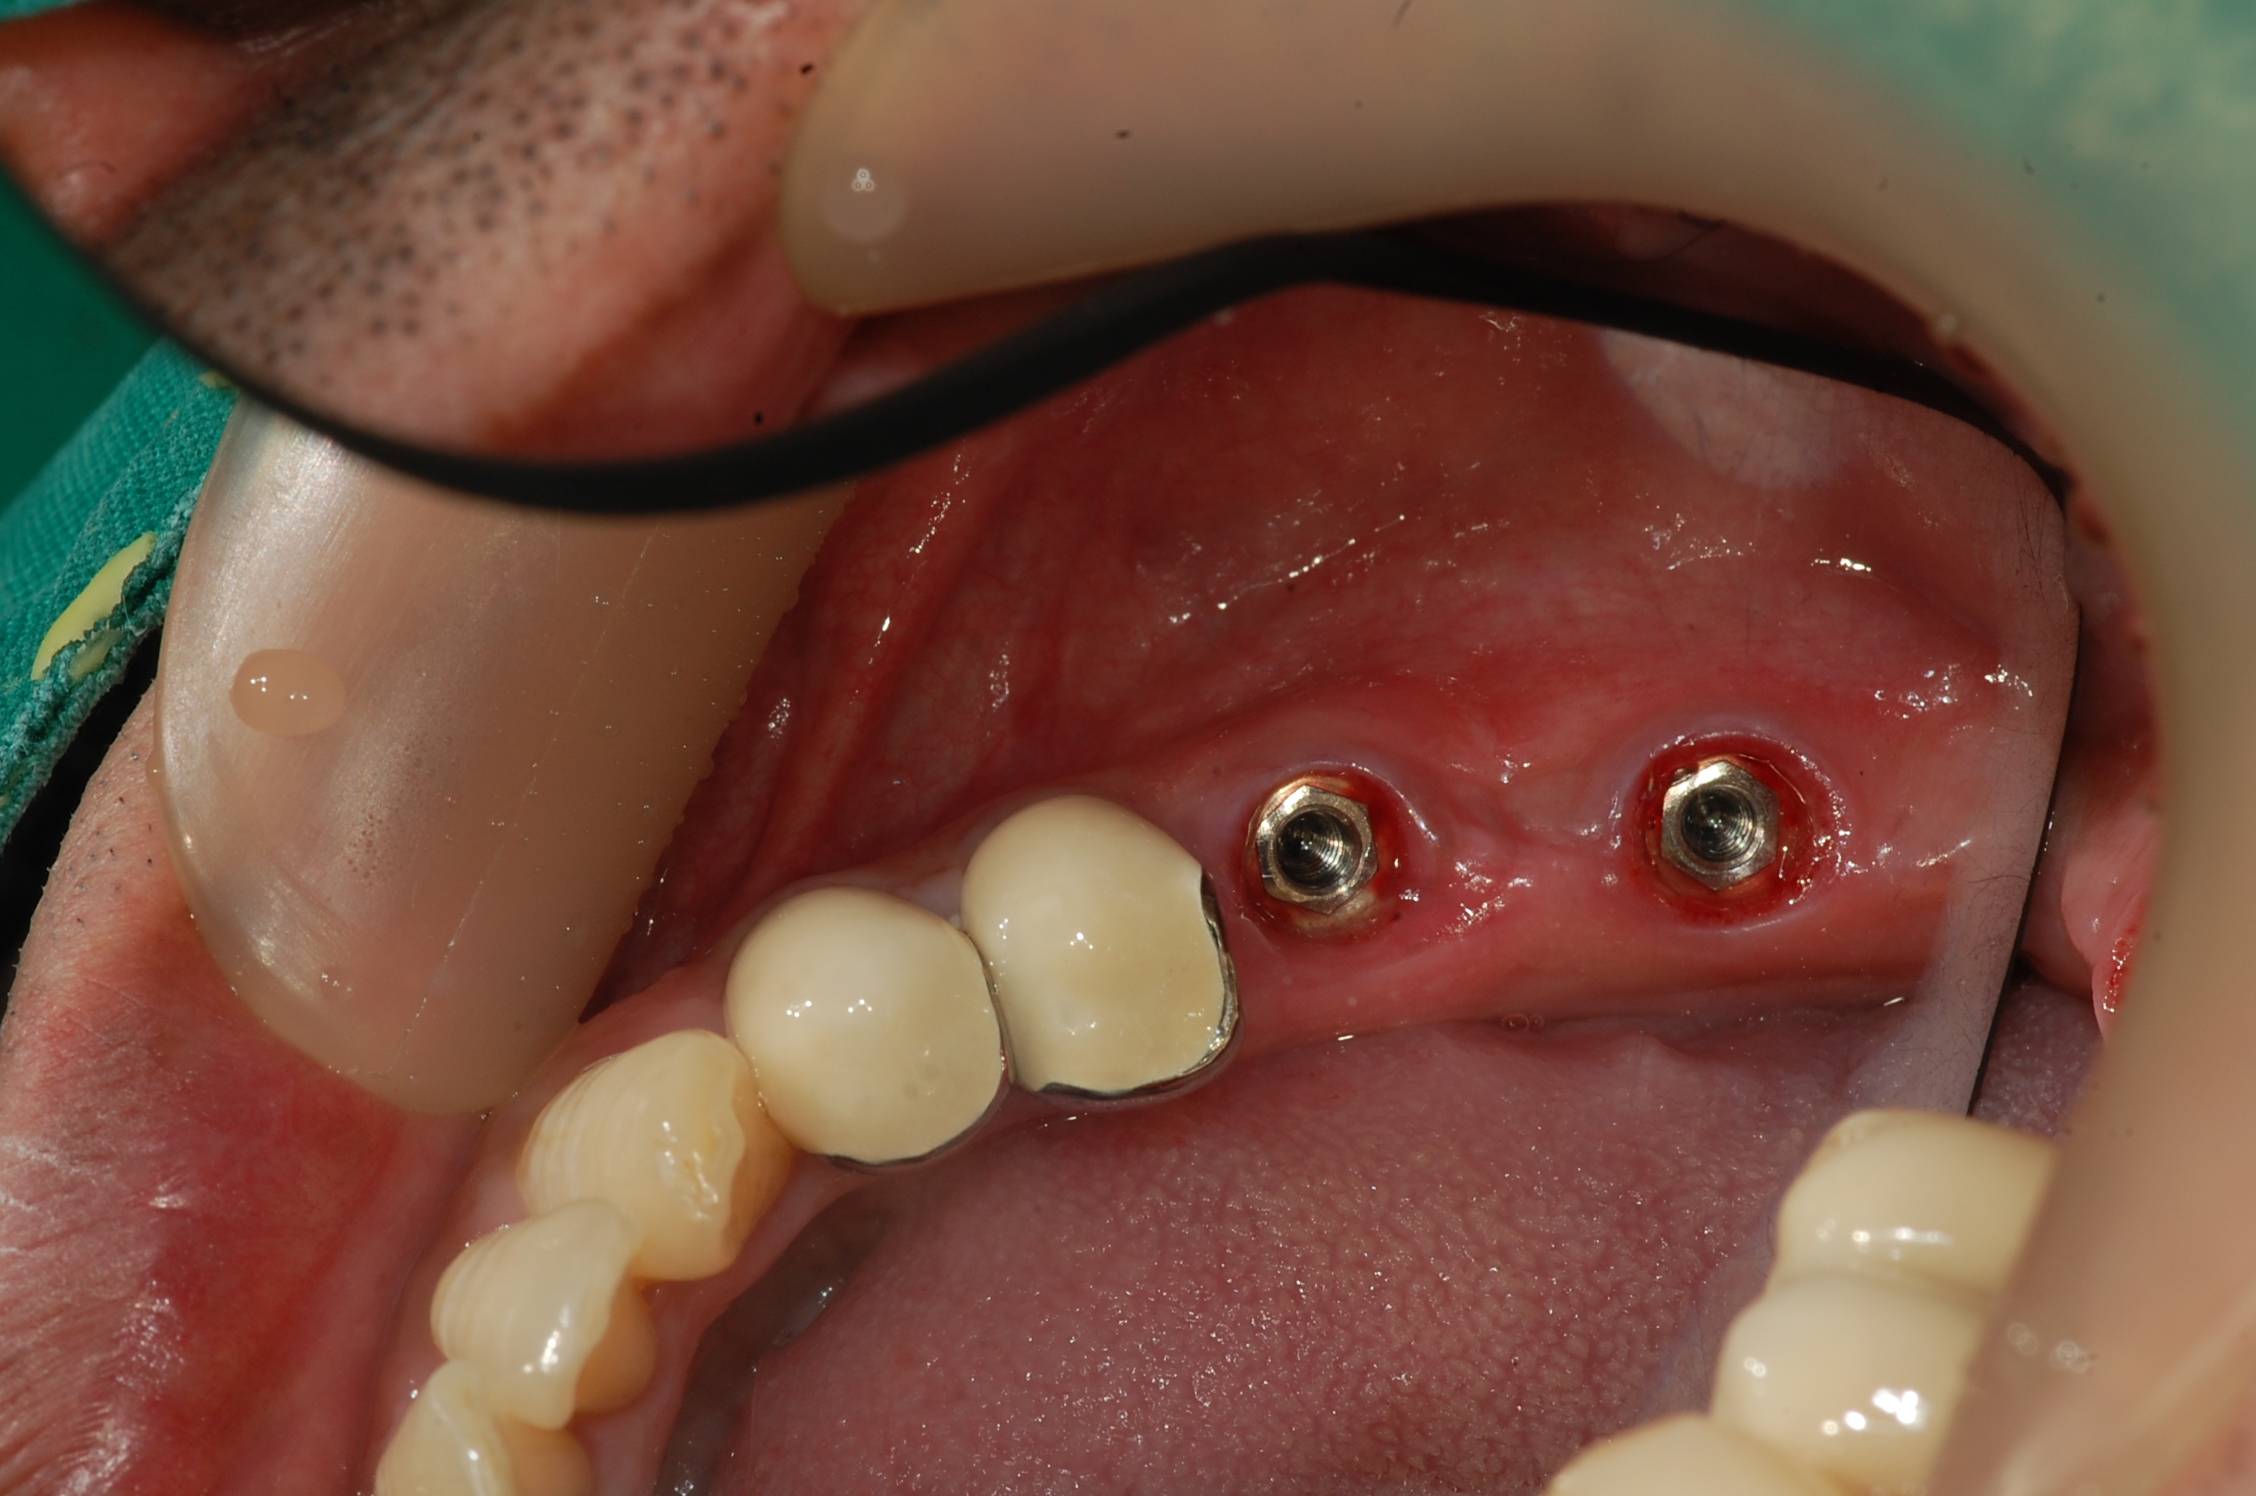

[임플란트] 제목 : 하악구치부

임플란트 및 보철치료